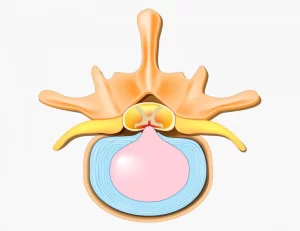

عود دیسک کمر: علت، علائم، درمان و پیشگیری

دیسک کمر بخشی نرم و ژلهای بین مهرههای ستون فقرات است که نقش ضربهگیر و انعطافدهنده ستون فقرات را ایفا میکند. هر دیسک شامل بخش